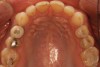

Fig 4. Preoperative occlusal view of upper arch.

Figure 4

A comprehensive examination was carried out, and preoperative photographs were taken (Figure 1 through Figure 4). The patient presented with fair oral hygiene and slight, generalized tissue inflammation. Caries and defective restorations were detected on teeth Nos. 4, 5, 13, and 14. The crown on tooth No. 12 was showing signs of leakage, and although the endodontic access cavity had been temporarily restored with composite, this endodontic re-treatment was acceptable and the tooth was otherwise symptom-free. Erosion was present on most of the posterior teeth and the cuspids, and abrasion was noted on teeth Nos. 4, 5, 10, 11, 20, 21, 22, 28, and 29. An examination of the patient's muscles, joints, and bite revealed no joint sounds, a normal range of motion, and negative joint load and immobilization tests.

The dentofacial examination revealed a low smile line with no incisor display when the lips were in repose. The anterior teeth were chipped and worn, and their overall color was darkened. The buccal corridors were deficient, and the failing crown on tooth No. 12 was visible in a full smile.